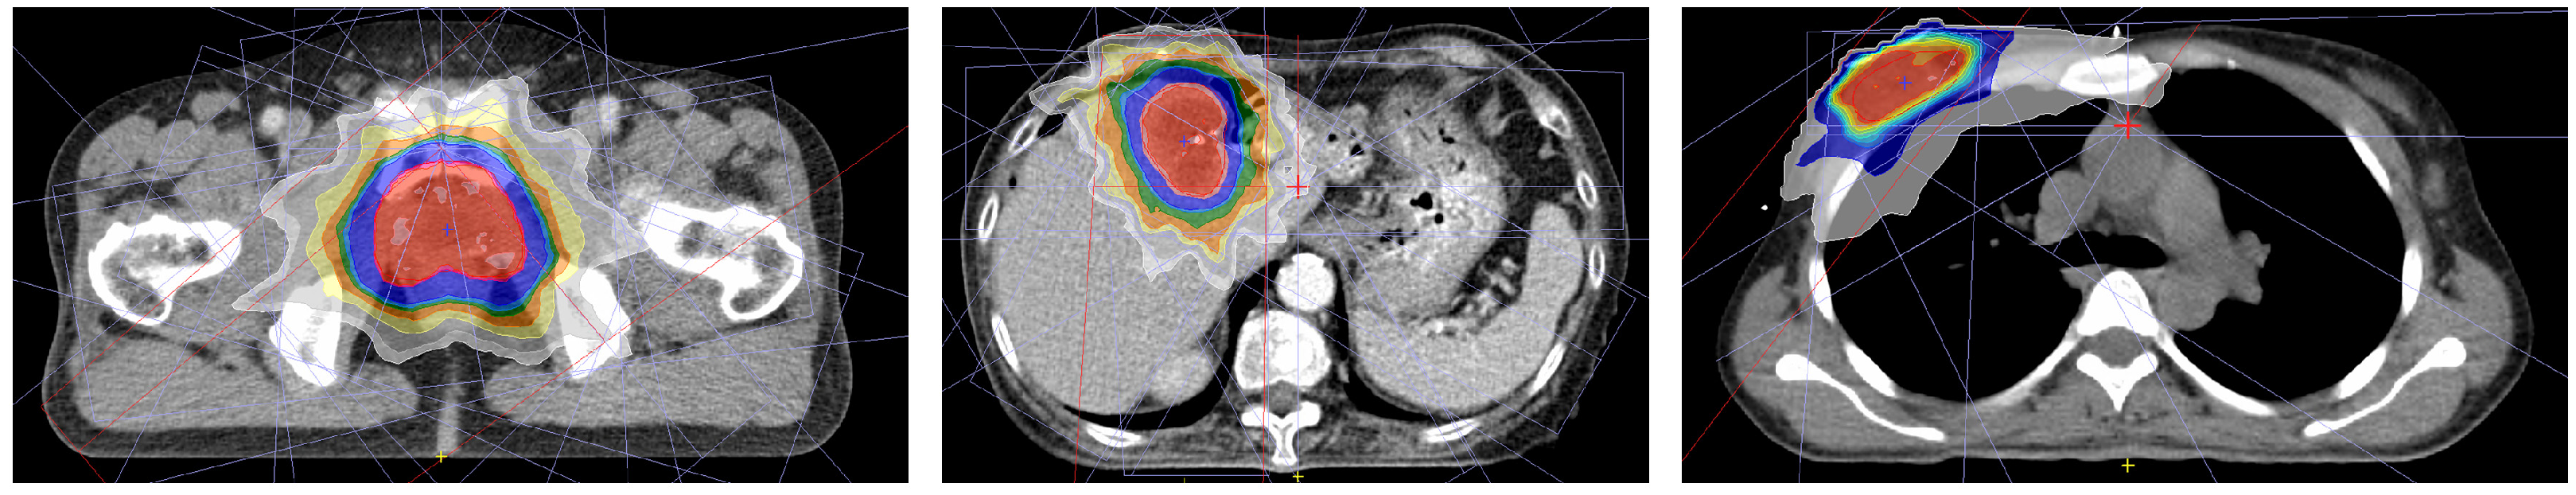

| Parameters | Prostate (n = 15) | Liver (n = 14) | Breast (n = 15) | |

|---|---|---|---|---|

| Gender | Male | 15 (100%) | 9 (64%) | 0 (0%) |

| Female | 0 (0%) | 5 (36%) | 15 (100%) | |

| Age | 30~39 | 0 (0%) | 0 (0%) | 3 (20%) |

| 40~49 | 0 (0%) | 0 (0%) | 3 (20%) | |

| 50~59 | 2 (13%) | 1 (7%) | 5 (33%) | |

| 60~69 | 5 (33%) | 6 (43%) | 4 (27%) | |

| 70~79 | 8 (53%) | 5 (36%) | 0 (0%) | |

| 80~89 | 0 (0%) | 2 (14%) | 0 (0%) | |

| Stage | T0~Tis | 0 (0%) | 0 (0%) | 5 (33%) |

| T1~T2 | 6 (40%) | 7 (50%) | 10 (67%) | |

| T3~T4 | 9 (60%) | 7 (50%) | 0 (0%) | |

| Target location | Right (Breast) | - | - | 10 (67%) |

| Left (Breast) | - | - | 5 (33%) | |

| Treatment technique | Palliative RT | 0 (0%) | 6 (43%) | 0 (0%) |

| Postoperative RT (boost) | 0 (0%) | 0 (0%) | 15 (100%) | |

| Salvage RT | 15 (100%) | 8 (57%) | 0 (0%) | |

| Prescribed dose | Only 57.6 Gy or 57.6 Gy for target and 45.6 Gy for LN | 30 Gy~50 Gy | 10 Gy | |

| Number of fractions | 24 | 10 | 5 | |

| Total number of plans used in this study | 360 | 140 | 75 | |